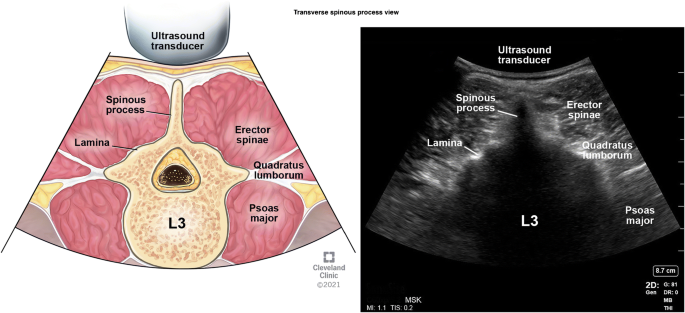

Transverse Spinous Process View

After identification of the appropriate interspace using the para-sagittal interlaminar view, the probe is turned 90° to obtain a transverse spinous process view (Fig. 12). The tip of the spinous process is identified as a white hyperechoic line with acoustic shadowing beneath it with a sloping lamina seen laterally (Fig. 13). This is the key view for the identification of midline (Fig. 5 probe position A) and the interspinous spaces between the consecutive spinous processes in obese patients. We recommend using M-mode line for determining the exact midline in this view (Fig. 14).

Fig. 13

Transverse spinous process view. (This image is produced with permission from Cleveland Clinic Center for Medical Art & Photography)